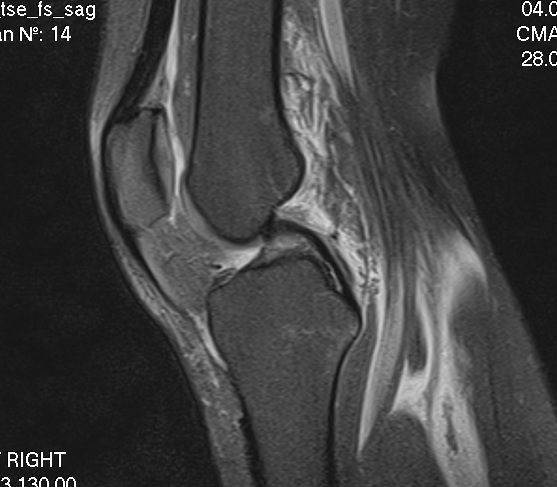

"Итак, после МРТ стало понятно, что у меня полностью оторвана передняя крестообразная связка. То есть, нога "гуляет" в колене. Это можно увидеть на фотографии МРТ, которую я прилагаю. На ней отчетливо видно заднюю крестообразную связку (она темная, сочетает бедренную и берцовую кость), а вот от передней видно только куски", - рассказала женщина.

Черновол уточнила, что без этой связки нога, как говорят специалисты, "не стабильна".

Экс-депутат рассказала, что ей нужна операция после того, как заживет другая надорванная связка. Причем, ту связку, которую порвали, уже не сшить - крестообразные связки на это не годятся. На лечение ей понадобится полгода.